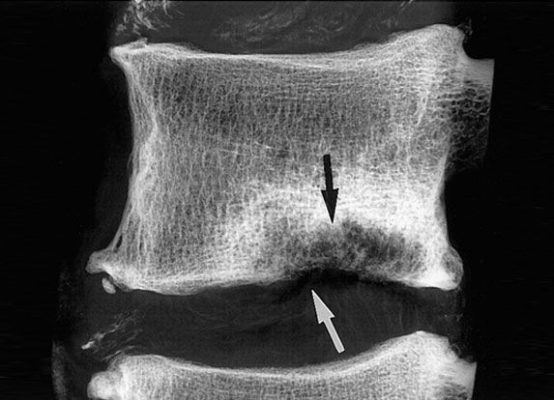

Грыжа Шморля — это разновидность межпозвоночных грыж. Такое заболевание нередко вызывает болевые ощущения,...

А.А. Жантурина, к.м.н. врач высшей категории Грыжа межпозвоночного диска – это дегенеративно-дистрофическое...